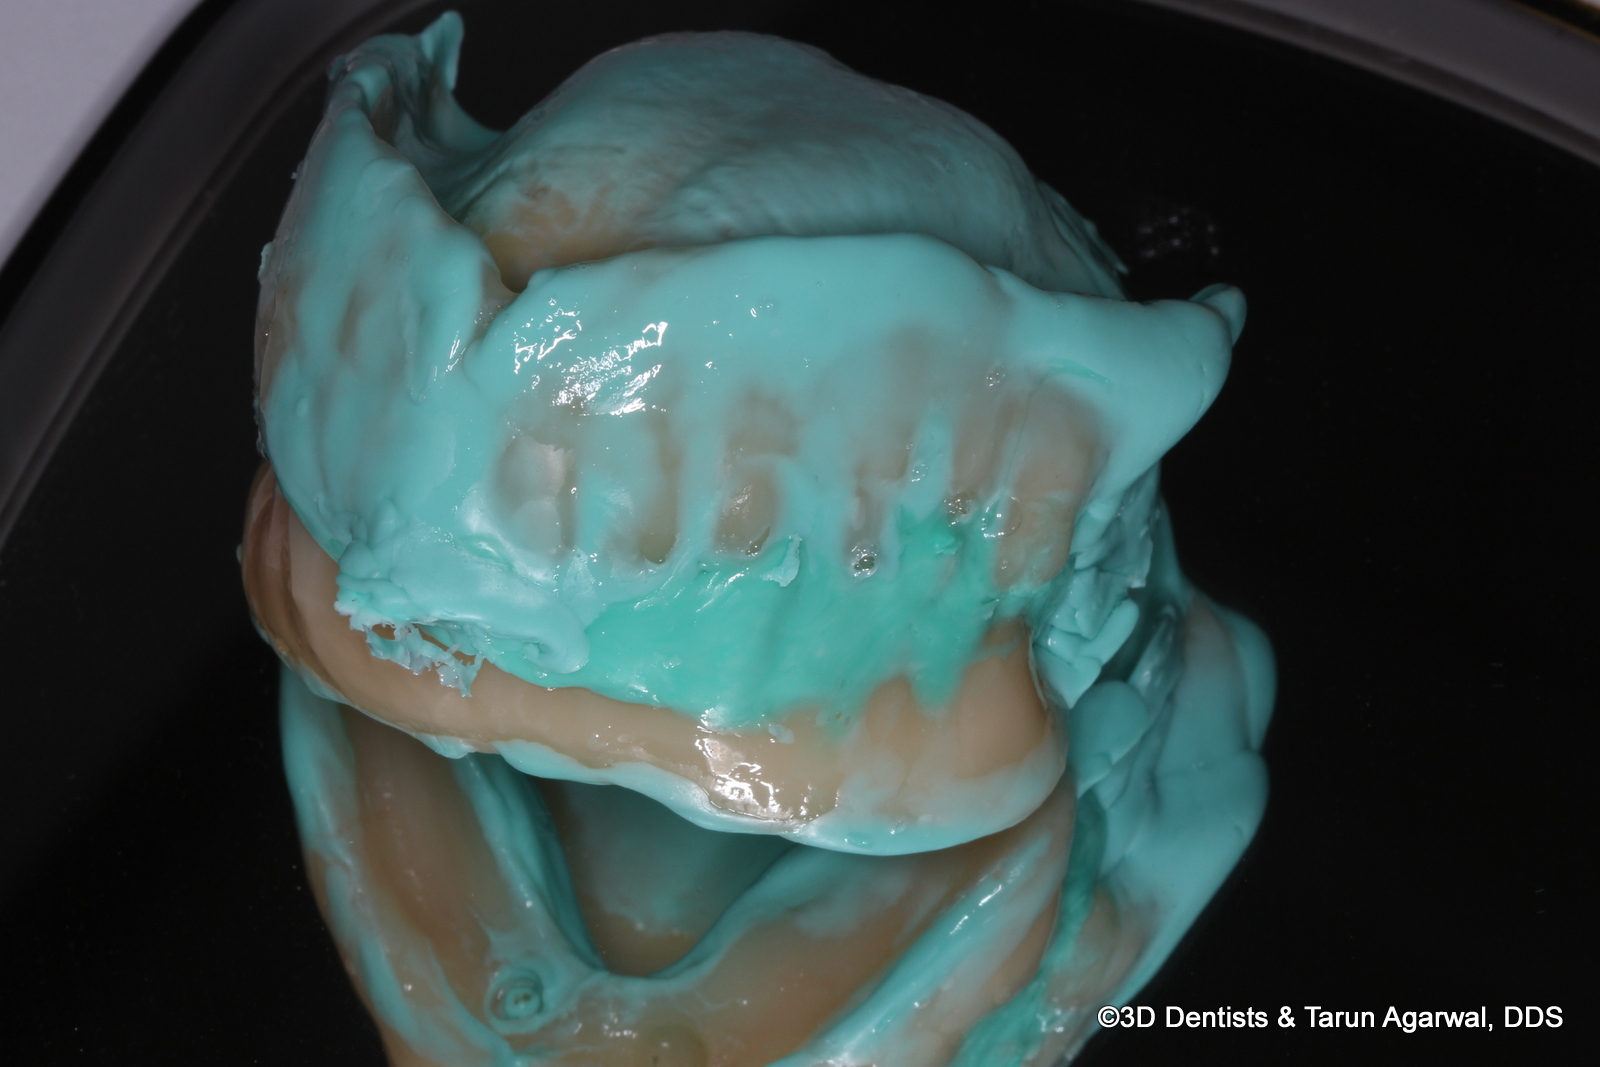

The printed try in dentures are quickly and easily relined with wash impression material for fabrication of the final prosthetic.